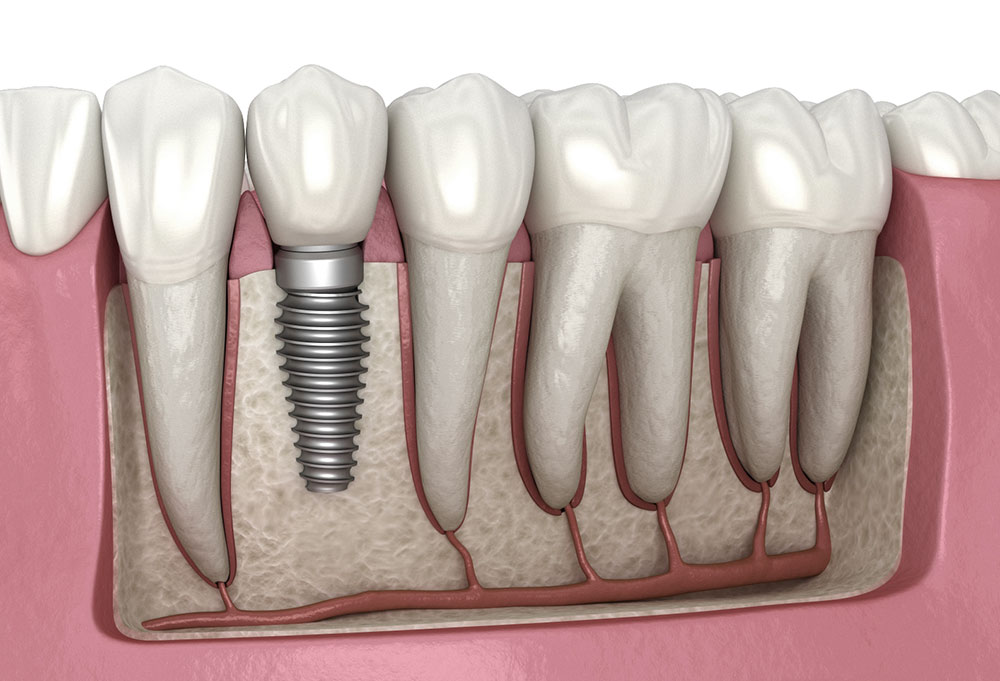

Современная стоматология: Железные зубные импланты